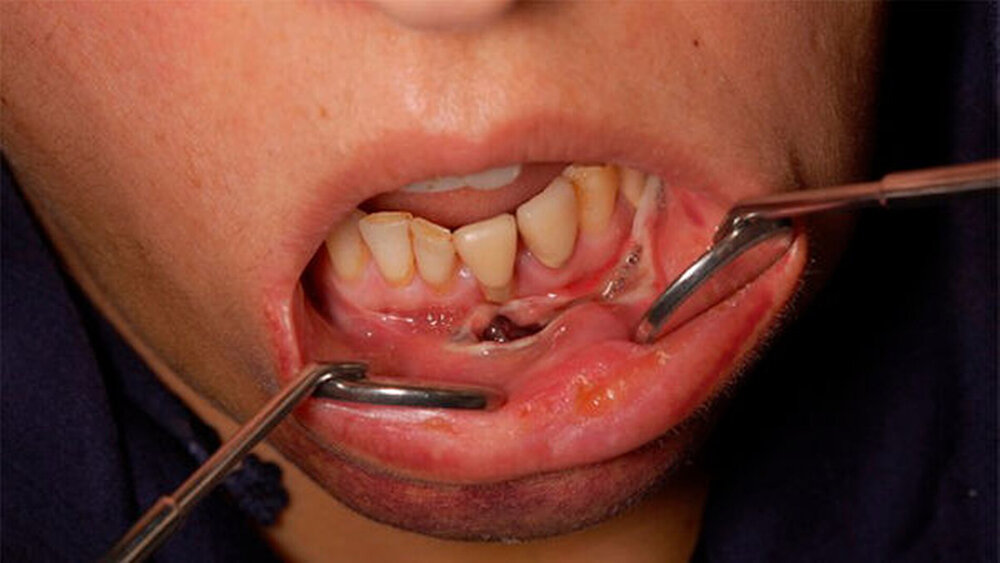

Intraoral entwickelte sich eine im Unterkiefer beidseits bis in die Prämolaren-Region reichende kirschrote bis violette pralle Vestibulumsschwellung, die sich im Mundboden bis auf die Höhe der Carunculae sublingualis ausdehnte. Eine Krepitation bei der Palpation lag nicht vor, die Zunge war schmerzbedingt nur eingeschränkt beweglich, der Rachenraum unauffällig.

Nachdem die Schwellung deutlich zunahm, erfolgte eine unter Lokalanästhesie durchgeführte intraorale Inzision am Punctum maximum sowie eine ausgiebige Spülung des Befundes mit physiologischer Kochsalzlösung und Polyhexanid. In die Wunde wurde ein Polyhexanid-Drainagestreifen eingelegt. Es folgten täglich zweimalige Spülungen und Streifenwechsel über vier Tage, worunter sich der Befund ab dem zweiten stationären Tag langsam regredient zeigte.